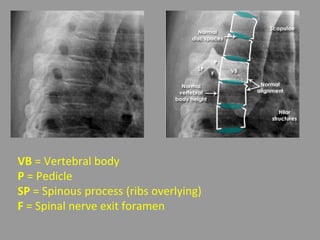

Thoracic spine - Systematic approach

• Alignment - Vertebral body alignment is

assessed by carefully matching the anterior

and posterior corners of the vertebral bodies

with the adjacent vertebra

• Bones - Gradual increase in vertebral body

height from superior to inferior

• Spacing - Disc spaces gradually increase in

VB = Vertebral body

P = Pedicle

SP = Spinous process (ribs overlying)

F = Spinal nerve exit foramen